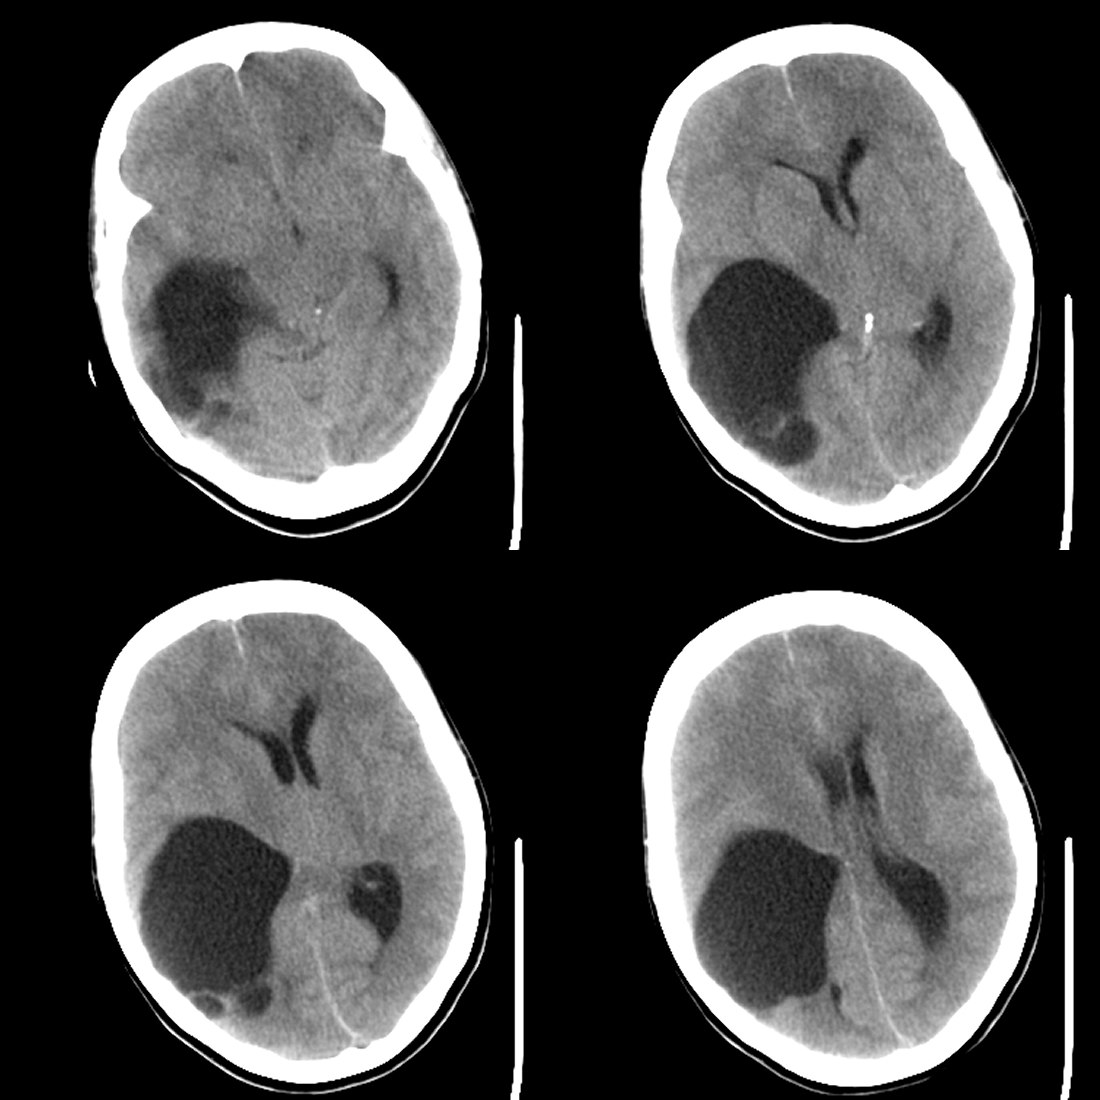

53岁女性,反复头痛,病史较长,今日加重数小时就诊。暂未作增强。

1)考虑蛛网膜下腔出血。2)右侧幕上半球相当于右侧侧脑室三角区区域巨大囊性占位性病变;考虑蛛网膜囊肿,不排除囊性胶质瘤。3)脑积水。4)大脑镰下疝。

考虑蛛网膜囊肿,右侧侧脑室后角及三角区受压变小,中线向左移位。病变与脑室不相通。没有脑积水!!